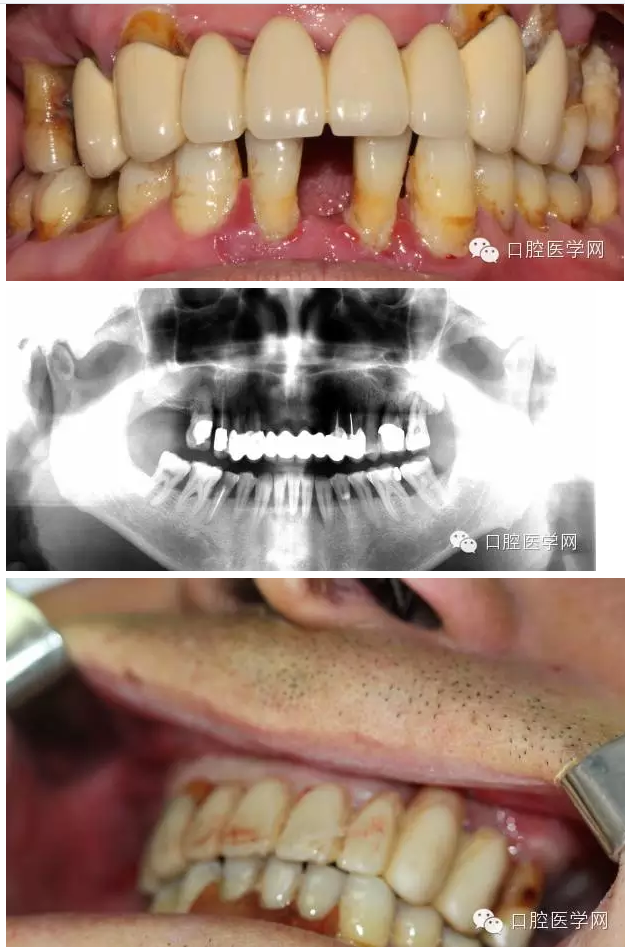

男,61歲,無過敏史

主訴:全口牙咬物無力來就診

現(xiàn)病史:一年來全口牙吃東西沒力氣,牙齒松動現(xiàn)要求治療

檢查:11、12、17、21、22、26缺 14到25 固定橋,且松動,且牙齦紅腫稍溢膿 15 26單冠,松動3度 16 27殘冠2度松動 42到32 缺一顆臨時活動義齒修復(fù) 42到32松動3度(+) 牙槽骨吸收超過根長三分之二無法保留35 36 45 46 殘冠 冷診痛 (45為根管治療后沒有修復(fù))其與牙不同程度松度 牙結(jié)石 牙齦紅腫。

初步診斷:1上頜不良修復(fù)體;2牙周炎;3 35 36 45 46牙髓炎

上頜導(dǎo)航手術(shù)前照片